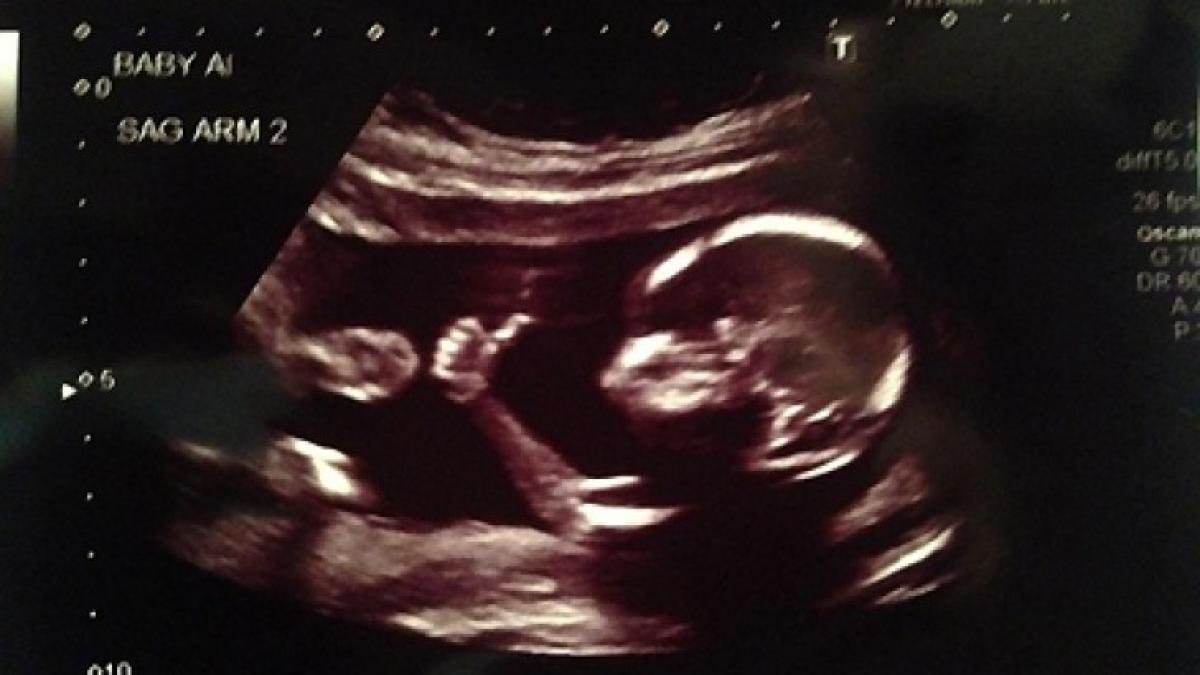

Ipostază senzațională a unui bebeluș în burtica mamei sale, surprinsă în timpul unui examen ecografic la care viitoarea mămică s-a prezentat.

Bebelușul, care se va naște curând, a fost surprins în momentul în care făcea un gest neobișnuit, scrie divahair.ro.

Cu degetul mare al mâinii drepte în sus și cu restul degetelor strânse în pumn, tipicul semn pentru OK, micuțul pare să transmită părinților că totul este în regulă.

Mesajul celui mai optimist bebeluș i-a făcut foarte fericiți pe viitorii părinți, mai ales că micuțul împarte această primă etapă a miracolului vieții cu un frate geamăn.

Imaginea surprinzătoare a devenit viral pe internet, reușind să strângă în doar câteva zile de la postare peste 2 milioane de vizualizări.